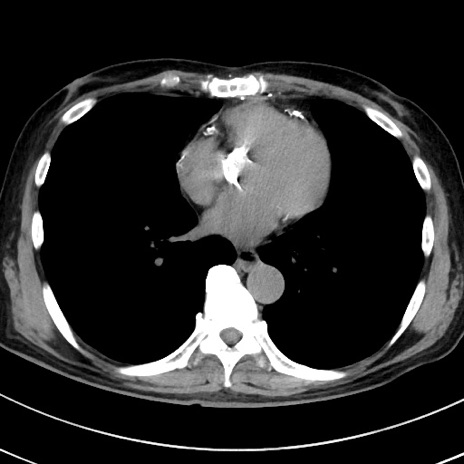

症例38(横断像)

【症例】70歳代 男性

【主訴】腹痛・嘔吐

【現病歴】昨晩より、嘔吐・腹痛あり。今朝になっても嘔吐あり。来院。

【既往歴】心臓バイパス手術、開腹胆摘、腸閉塞

【身体所見】BP 107/71mmHg、HR 116/min、腹部:平坦、軟、下腹部に軽度圧痛あり。反跳痛なし。

【データ】WBC 15100、CRP 0.32